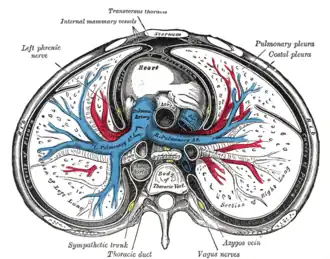

A transverse section of the thorax, showing the contents of the middle and the posterior mediastinum.

A transverse section of the thorax, showing the contents of the middle and the posterior mediastinum.

Middle inferior mediastinum

Bounded: pericardial sac – It contains the vital organs and is classified into the serous and fibrous pericardium.[4]

Posterior inferior mediastinum

Is bounded:

- Anteriorly by (from above downwards): bifurcation of trachea; pulmonary vessels; fibrous pericardium and posterior sloping surface of diaphragm

- Inferiorly by the thoracic surface of the diaphragm (below);

- Superiorly by the transverse thoracic plane;

- Posteriorly by the bodies of the vertebral column from the lower border of the fifth to the twelfth thoracic vertebra (behind);[4]

- Laterally by the mediastinal pleura (on either side).